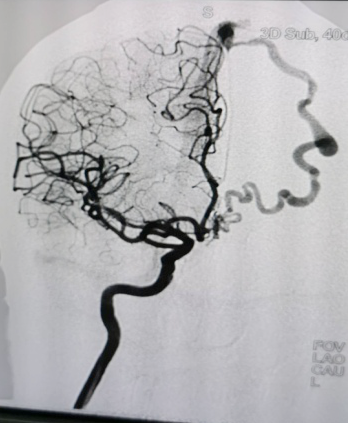

〖医线前沿〗市医院神经外科成功完成高难度硬脑膜动静脉瘘介入栓塞术

▲三维重建

▲术中情况

此类疾病常规开刀手术无法完成,必须通过神经介入血管内治疗,和家属沟通后,在外请专家指导下,在介入科、手术麻醉科的大力协助下,神经外科二病区神经介入脑血管病诊疗团队顺利为患者实施手术,手术过程顺利,术后造影提示眼动脉血流缓慢但视网膜中央动脉血流通畅,视网膜染色正常,视力正常,为防止眼动脉血栓闭塞视网膜中央动脉,给予低分子肝素钙皮下注射。术后患者症状即刻消失,现正继续后续治疗。

▲从左到右:术后右侧颈内动脉正位造影、术后右侧颈内动脉侧位造影

神经外科二病区在我院先行开展了脑血管造影检查,此次又率先开展神经介入治疗,不仅实现了陇南市及周边地区之前仅仅能做造影检查到现在能够完成介入治疗的重大跨越,而且填补了我市及周边地区介入治疗的空白,也标志着我市乃至甘肃南部地区神经介入发展进入新时代。